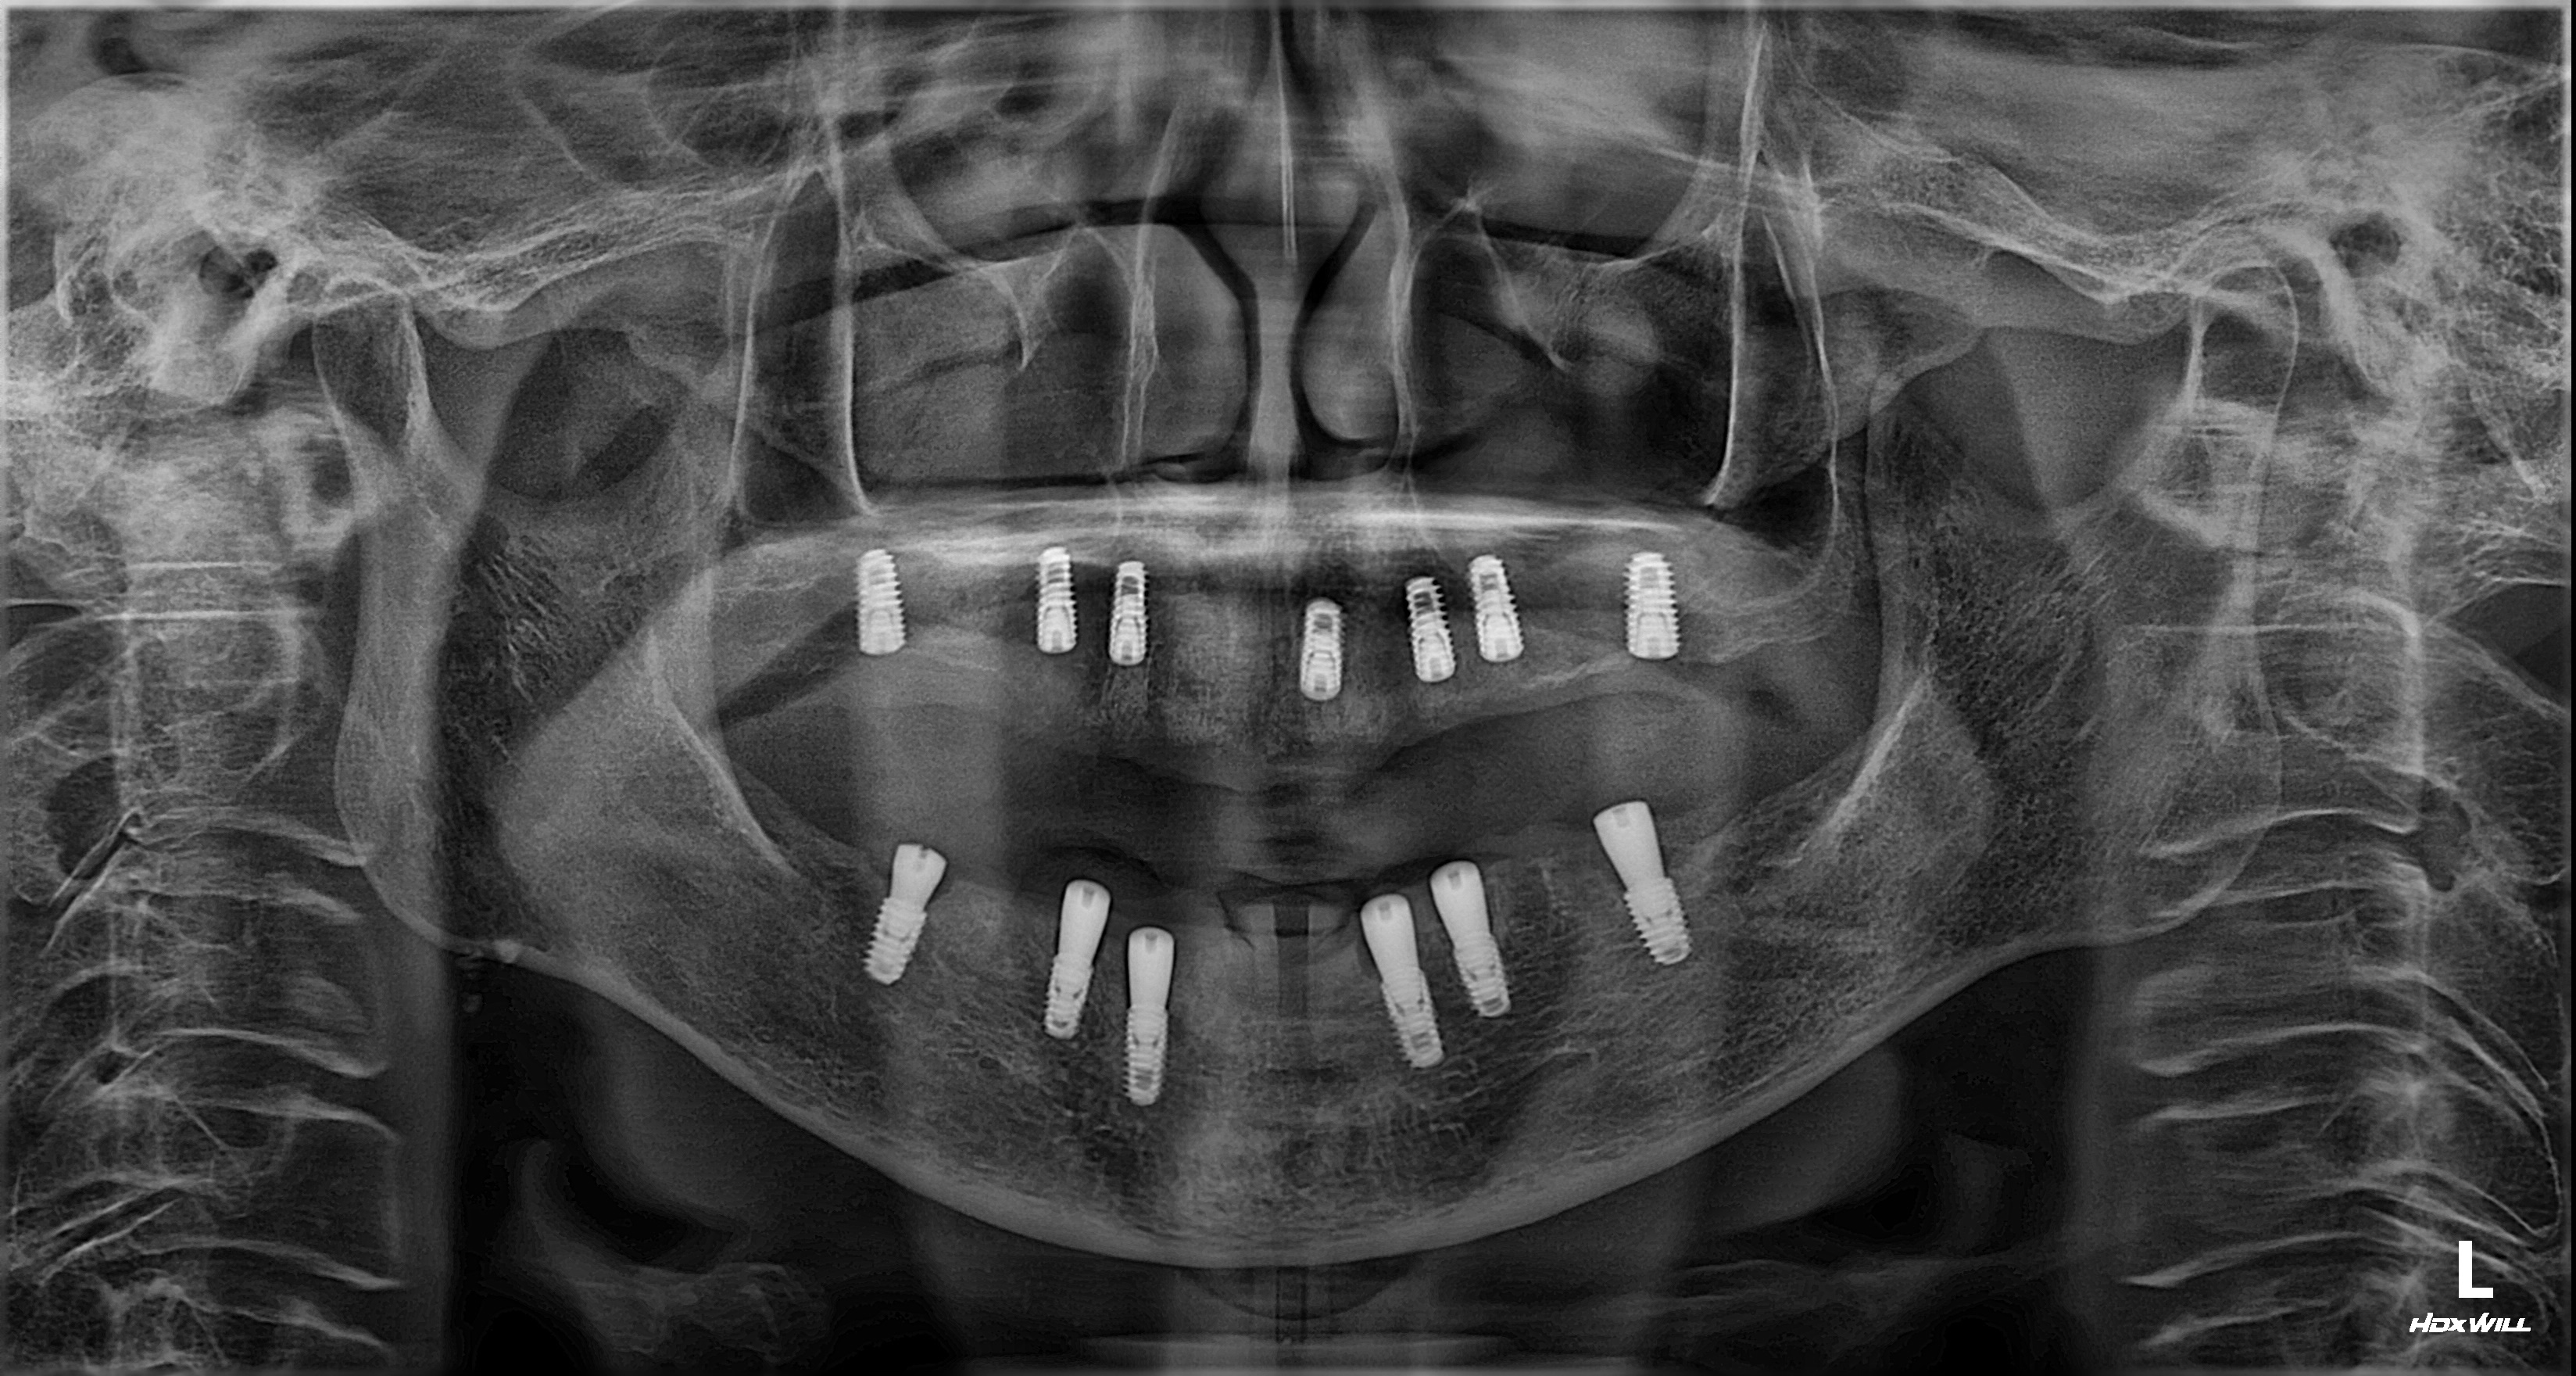

촬영일시: 2025.06.05